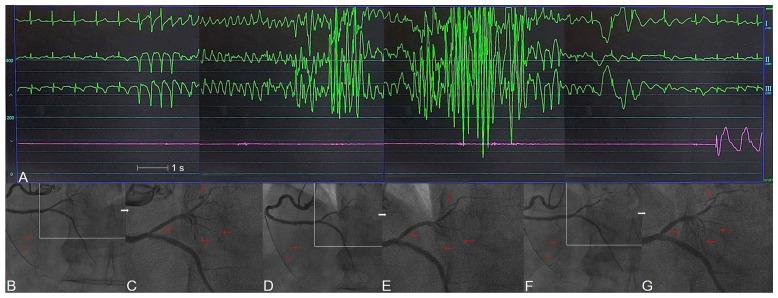

Although heart failure (HF) is a clinical syndrome that becomes worse over time, certain cases can be reversed with appropriate treatments. While coronary artery spasm (CAS) is still underappreciated and may be misdiagnosed, ischemia due to coronary artery disease and CAS is becoming the single most frequent cause of HF worldwide. CAS could lead to syncope, HF, arrhythmias, and myocardial ischemic syndromes such as asymptomatic ischemia, rest and/or effort angina, myocardial infarction, and sudden death. Albeit the clinical significance of asymptomatic CAS has been undervalued, affected individuals compared with those with classic Heberden's angina pectoris are at higher risk of syncope, life-threatening arrhythmias, and sudden death. As a result, a prompt diagnosis implements appropriate treatment strategies, which have significant life-changing consequences to prevent CAS-related complications, such as HF. Although an accurate diagnosis depends mainly on coronary angiography and provocative testing, clinical characteristics may help decision-making. Because the majority of CAS-related HF (CASHF) patients present with less severe phenotypes than overt HF, it underscores the importance of understanding risk factors correlated with CAS to prevent the future burden of HF. This narrative literature review summarises and discusses separately the epidemiology, clinical features, pathophysiology, and management of patients with CASHF.

尽管心力衰竭(HF)是一种随着时间推移而恶化的临床综合征,但某些病例可以通过适当的治疗得到逆转。虽然冠状动脉痉挛(CAS)仍然未被充分认识,并且可能被误诊,但由于冠状动脉疾病和 CAS 引起的缺血已成为全球 HF 的单一最常见原因。CAS 可导致晕厥、HF、心律失常和心肌缺血综合征,如无症状性缺血、静息和/或劳力性心绞痛、心肌梗死和猝死。尽管无症状性 CAS 的临床意义被低估,但与经典 Heberden 心绞痛患者相比,受影响的个体发生晕厥、危及生命的心律失常和猝死的风险更高。因此,及时诊断并采取适当的治疗策略,对预防与 CAS 相关的并发症(如 HF)具有重大的改变生活的意义。虽然准确的诊断主要取决于冠状动脉造影和激发试验,但临床特征可能有助于决策。由于大多数与 CAS 相关的 HF(CASHF)患者的表型比明显 HF 患者的表型更轻,因此强调了了解与 CAS 相关的风险因素以预防未来 HF 负担的重要性。本叙述性文献综述分别总结和讨论了 CASHF 患者的流行病学、临床特征、病理生理学和管理。